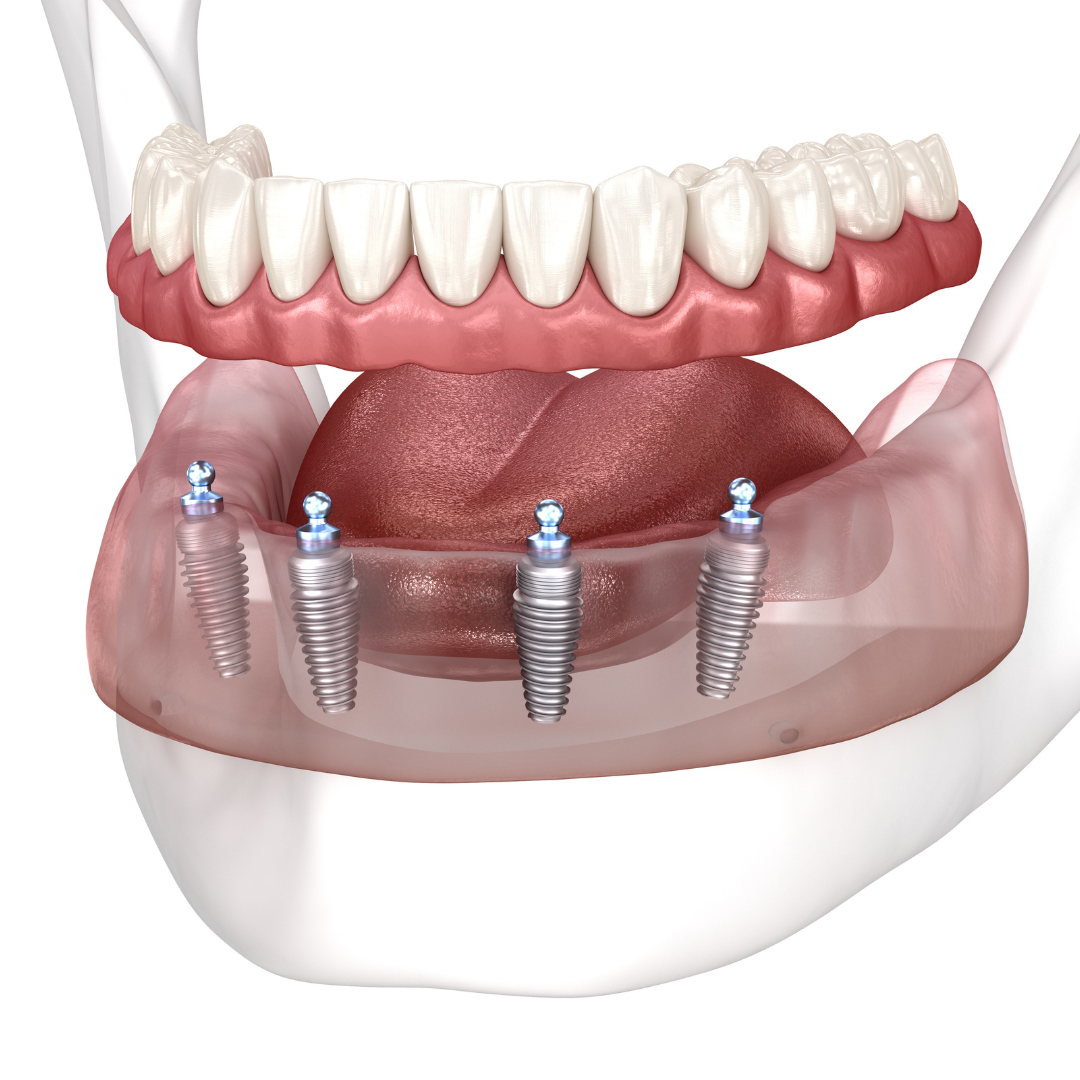

So, how do they work?

Every single dental implant consists of three parts - the implant, the abutment, & the crown. The implant is made of medical grade titanium. This part is surgically placed into the patient’s jaw bone and left to heal for 4-6 months afterwards.

This implant piece acts as the foundation for the rest of the tooth. Once the bone around the site has healed, the abutment and crown are placed on top of the implant. The end result is a beautiful, natural-looking new tooth!

Few people will ever be able to tell the difference between your implants and your real teeth.